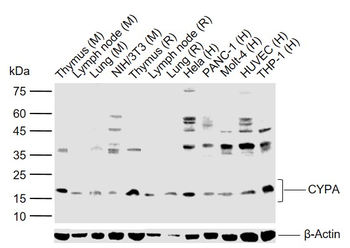

Anti-Cyclophilin A/PPIA Antibody [orb19174]

FC, ICC, IF, IHC, IHC-Fr, WB

Human, Mouse, Rat

Rabbit

Polyclonal

Unconjugated

10 μg, 100 μgCYPA Rabbit Polyclonal Antibody [orb100498]

FC, IF, IHC-Fr, IHC-P, WB

Bovine, Canine, Porcine, Rabbit

Human, Mouse, Rat

Rabbit

Polyclonal

Unconjugated